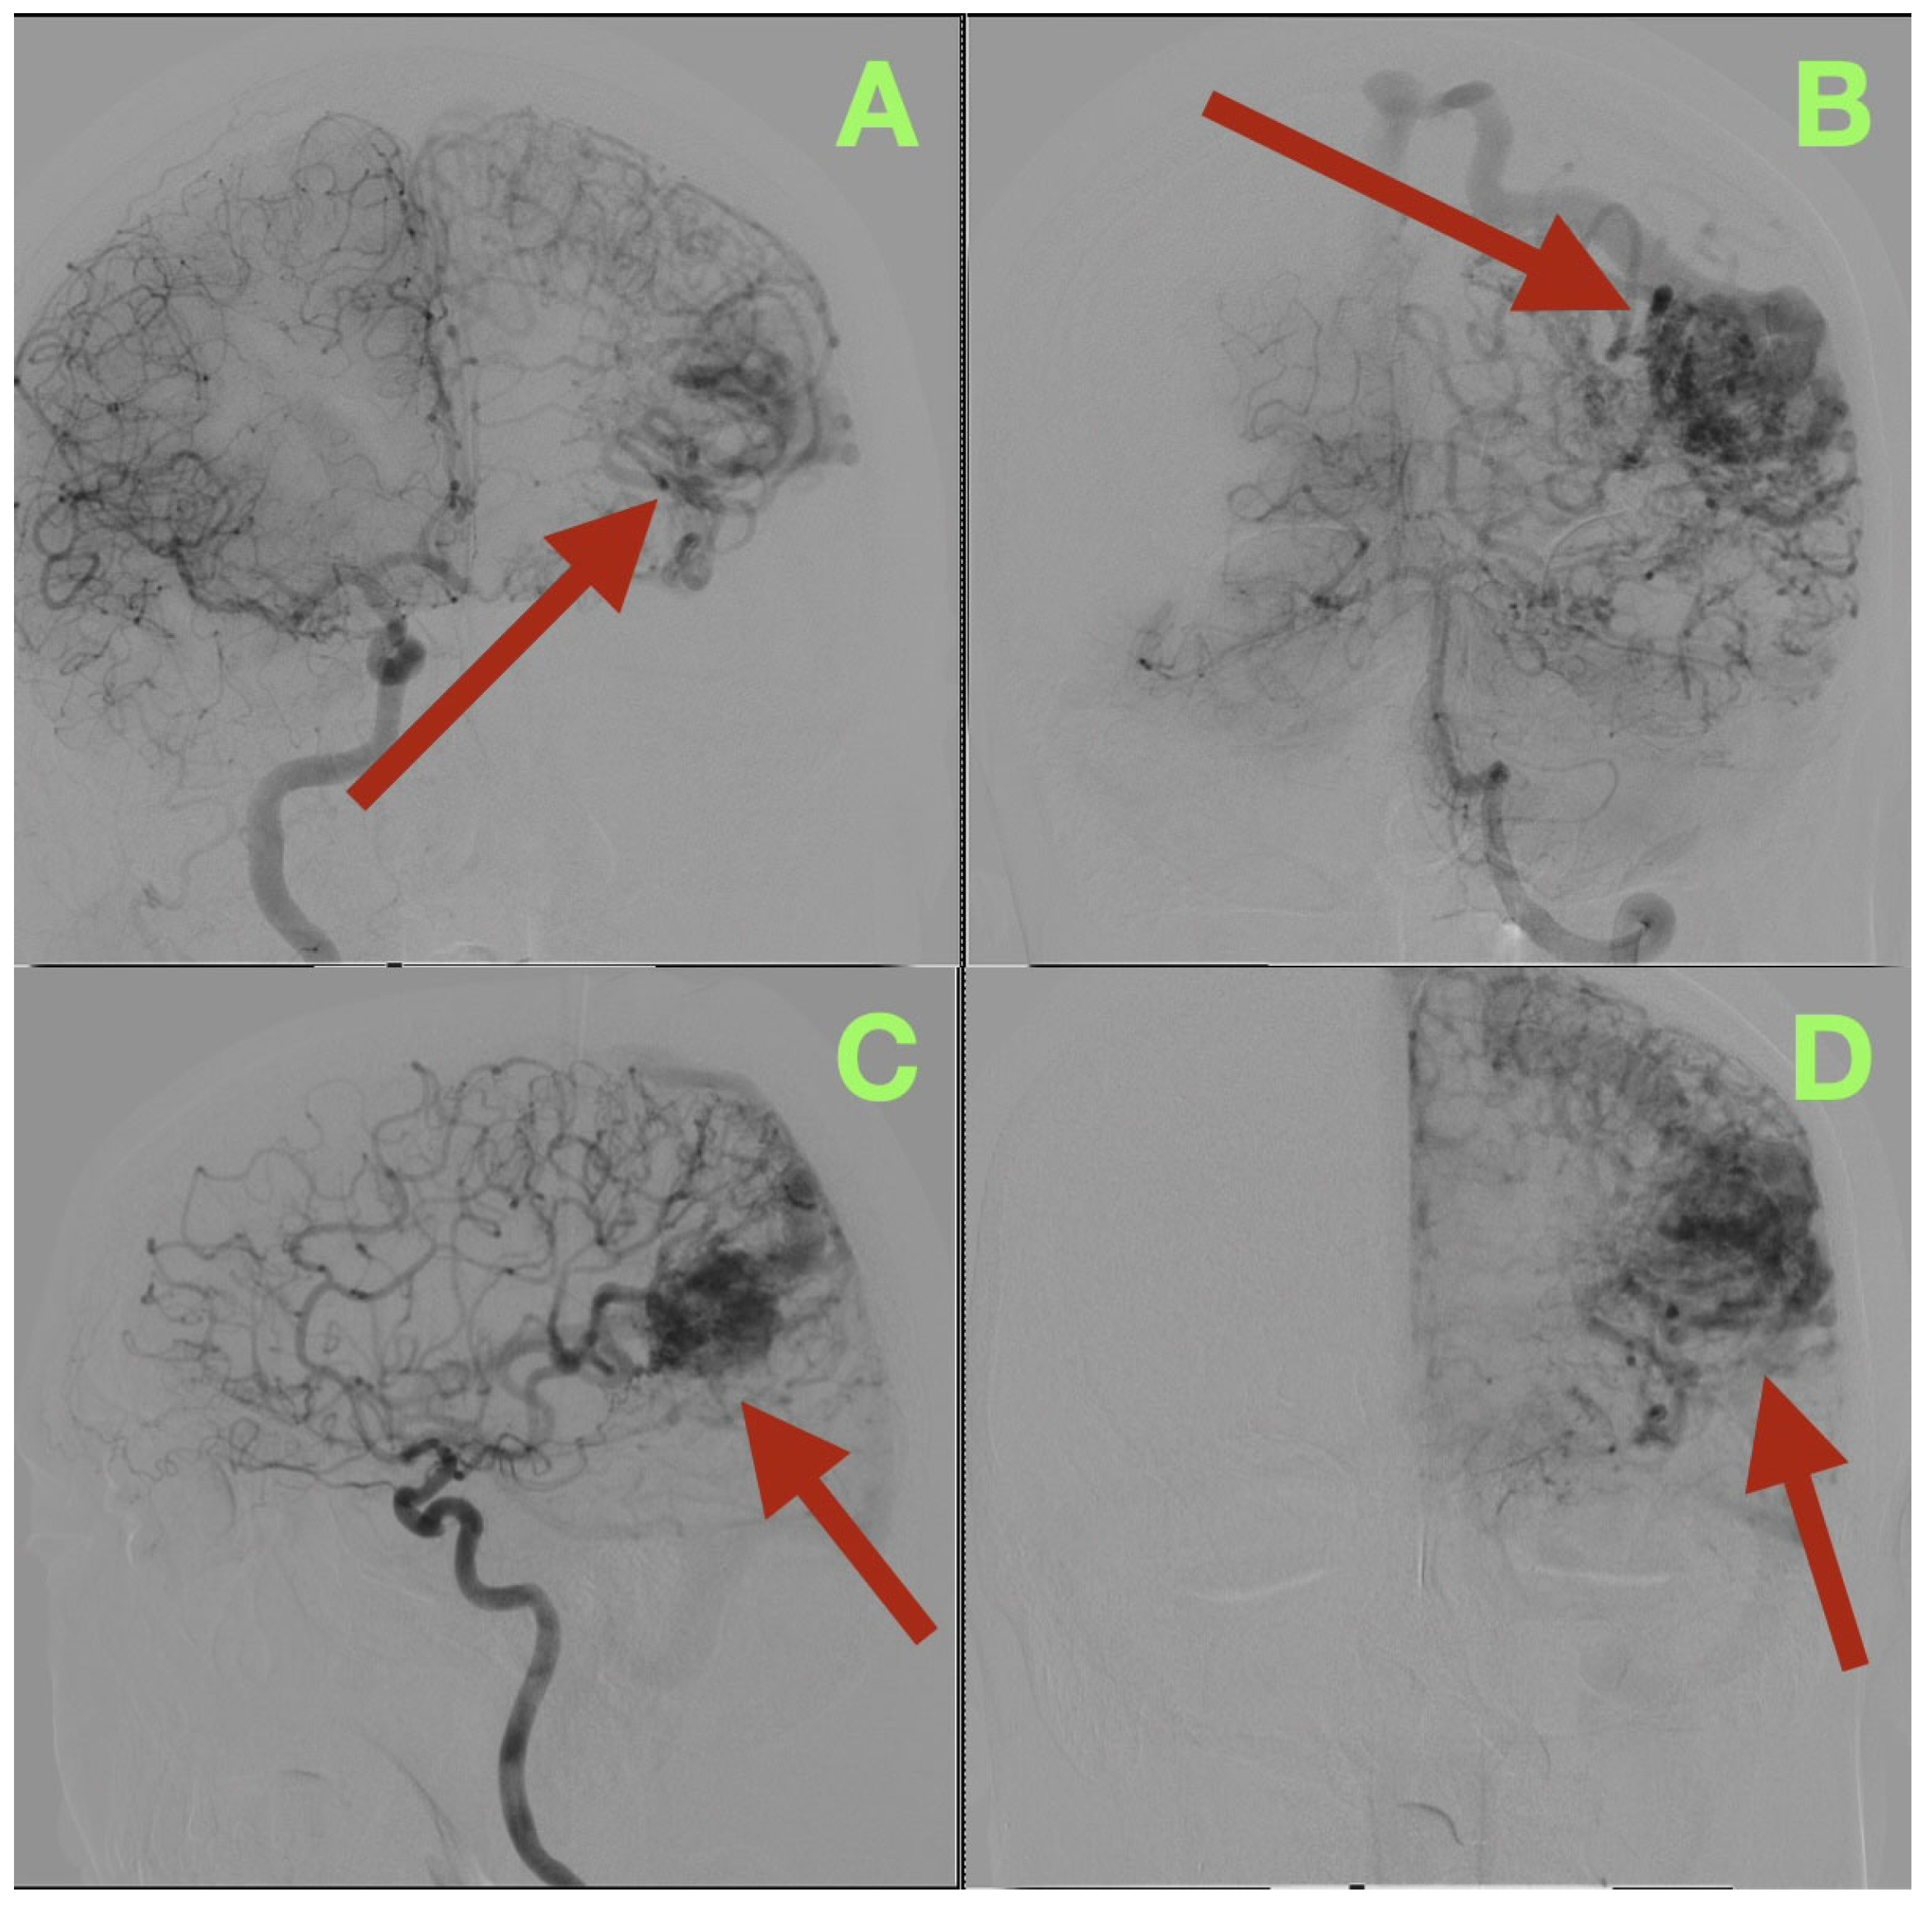

The AVM was found to receive blood supply from four different vascular territories: distal posterior cerebral artery (P4) branches from the calcarine and lingual cortices, distal middle cerebral artery (M4) branches from the temporal lobe, a branch from the anterior cerebral artery (A4) from the medial surface of the hemisphere, and a small twig from the superior cerebellar artery ascending along the tentorial edge (Figure 1A–D and Figure 2A,B). These multiple and diverse arteries converge and create a complex multi-directional shunt that supports high velocity flow and maintains parenchymal perfusion through inter-territorial anastomoses. The MCA feeders penetrate the posterior Sylvian fissure, which correlates with the patient’s expressive language hesitancy and phonemic errors. The PCA branches course through the temporal horn roof, which correlates with the patient’s right inferior quadrantanopia. The ACA feeds the superior aspect of the nidus bordering the paracentral lobule and correlates with the mild contralateral pyramidal hyperreflexia.

Three-dimensional rotational angiography provided further details about the relationship between the nidus and the surrounding cortex. The nidus is densely packed with tortuous vessels that form a tangential interface with eloquent cortical regions (Figure 2A,B). The short pial feeder enters at nearly perpendicular angles and the venous outflow exits tangentially along the cortical surface. The configuration of the feeder and outflow results in the least amount of transparenchymal penetration possible, however the result of such is maximal cortical hemodynamic exposure. The hemodynamic pattern corresponds directly to the patient’s neurologic deficits: the feeders from the posterior temporal and angular cortices caused the patient’s expressive aphasia secondary to arcuate fasciculus disruption; the occipital extension caused the patient’s contralateral visual field loss; and the periventricular venous congestion caused the patient’s mild right sided pyramidal dysfunction.

Figure 2. Three-dimensional rotational angiography reconstructions. (A): Left lateral oblique view showing the compact nidus (arrow) embedded beneath the posterior superior temporal and angular gyri. The close spatial relationship to the arcuate fasciculus and Meyer’s loop explains the patient’s expressive aphasia and right inferior quadrantanopia. (B): Posterior oblique projection illustrating the deep extension of the nidus toward the occipital surface (arrow) and the tangential entry of short pial feeders from M4 and P4 branches. The surrounding venous system demonstrates smooth, ectatic channels draining into both the superior sagittal and transverse-sigmoid sinuses, confirming a mixed superficial-deep outflow pattern.